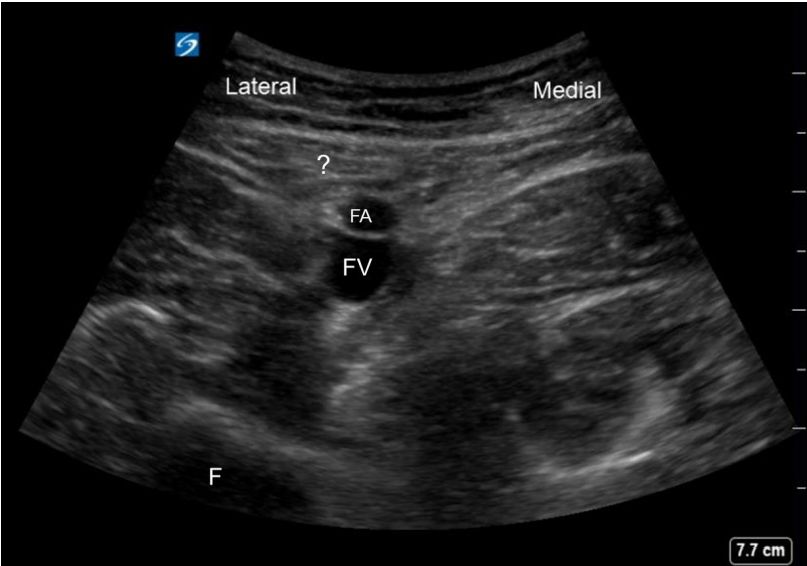

98. 進行 Adductor canal block (ACB)時,除 superficial femoral artery 尚須辨認重要的 thigh muscles,請問下圖標示” ? “是哪一條肌肉FA: superficial femoral arteryFV: femoral veinF: Femur(A) Gracilis muscle(B) Vastus lateralis muscle(C) Semitendinosus muscle(D) Sartorius muscle